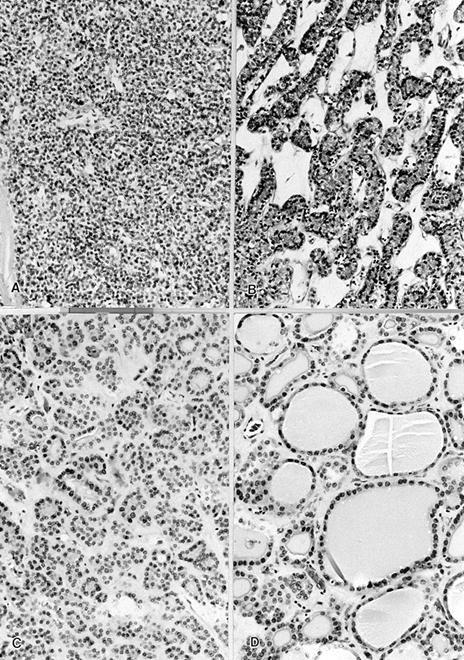

Microscopic (histologic) description

- Architecturally and cytologically different from surrounding gland

- Compression signs in surrounding thyroid tissue

- Encapsulated; thin or moderately thick capsule

- Architectural patterns (can be seen in any combination)

- Normofollicular (simple): size similar to normal thyroid follicles

- Microfollicular (fetal): smaller follicles, small amount of intraluminal colloid

- Macrofollicular (colloid): large follicles, flattened epithelium, abundant colloid

- Solid / trabecular (embryonal): minimal or no colloid

- Focal papillary pattern, occasionally; especially in hyperfunctioning adenoma and follicular adenoma with papillary hyperplasia

- Cuboidal to low columnar cells

- Small round nuclei, smooth nuclear boundary, uniformly hyperchromatic or euchromatic, dense chromatin, absent nuclear features of papillary thyroid carcinoma, nuclear score 0 or 1 (JAMA Oncol 2016;2:1023)

- Inconspicuous nucleoli

- No capsular or vascular invasion after thorough sampling (at least 10 blocks)

Microscopic (histologic) images

Contributed by Shipra Agarwal, M.D., Andrey Bychkov, M.D., Ph.D., Mark R. Wick, M.D., Asmaa Gaber Abdou, M.D. and AFIP

Patterns:

Not invasion: